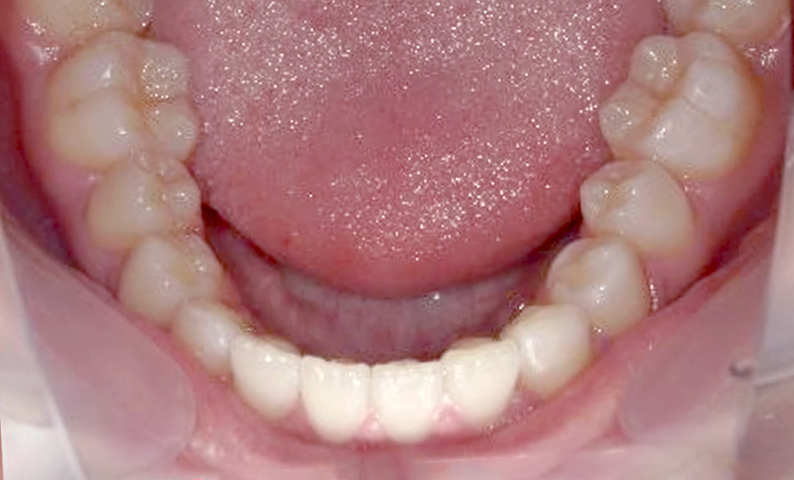

症例_001 上下顎の部分矯正

治療期間:12ヶ月金額:54万円+税女性前歯のガタガタ逆八の字